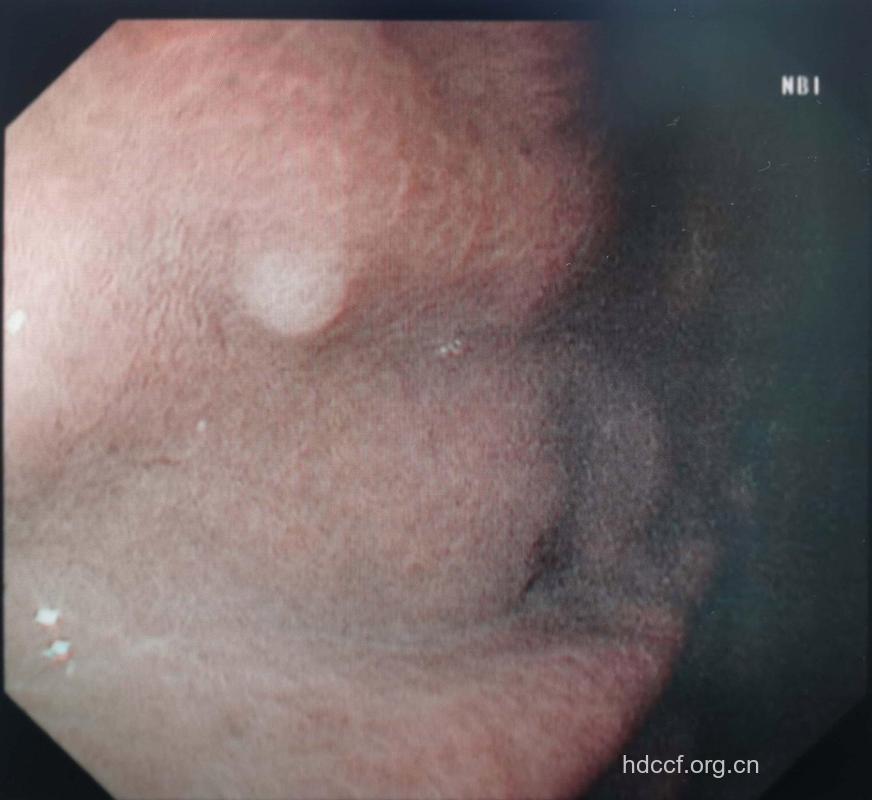

胃息肉是指胃黏膜局限性良性隆起病变。本病早期或无并发症时多无症状。从病理上将胃息肉分为两类:增生性或再生性息肉和腺瘤性息肉。胃息肉什么症状?胃病专家说,胃息肉在早期或无并发症时多数无症状。出现症状时常表现为上腹隐痛。

1.本病早期或无并发症时多无症状:出现症状时常表现为上腹隐痛、腹胀、不适,少数可出现恶心、呕吐。合并糜烂或溃疡者可有上消化道出血,多表现为粪潜血试验阳性或黑便,呕血少见。位于幽门部的带蒂息肉,可脱入幽门管或十二指肠,而出现幽门梗阻的表现。息肉生长于贲门附近时可有吞咽困难。

专家指出,胃息肉长的都很小,不到一厘米,增生性息肉基本上属于良性病变,仅少数人一旦增生性息肉长大,可引起消化不良、腹痛不适等症状,还会发生上消化道出血怀才就像怀孕,时间久了才能让人看出来,也会癌变。